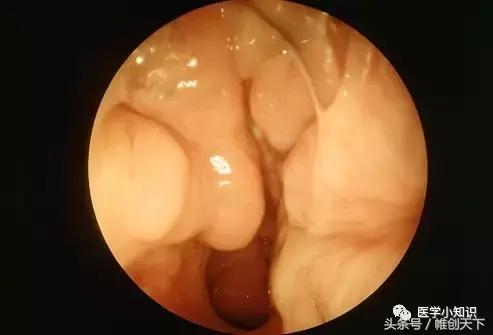

鼻息肉

鼻窦长期处于发炎状态使得窦膜加厚、肿胀,鼻腔黏膜出现水肿样改变,形成像葡萄样聚集的鼻息肉(如图所示)。鼻息肉形成后进一步堵塞了鼻窦的引流通道阻碍了粘液的持续流动,进一步加重了鼻窦炎。